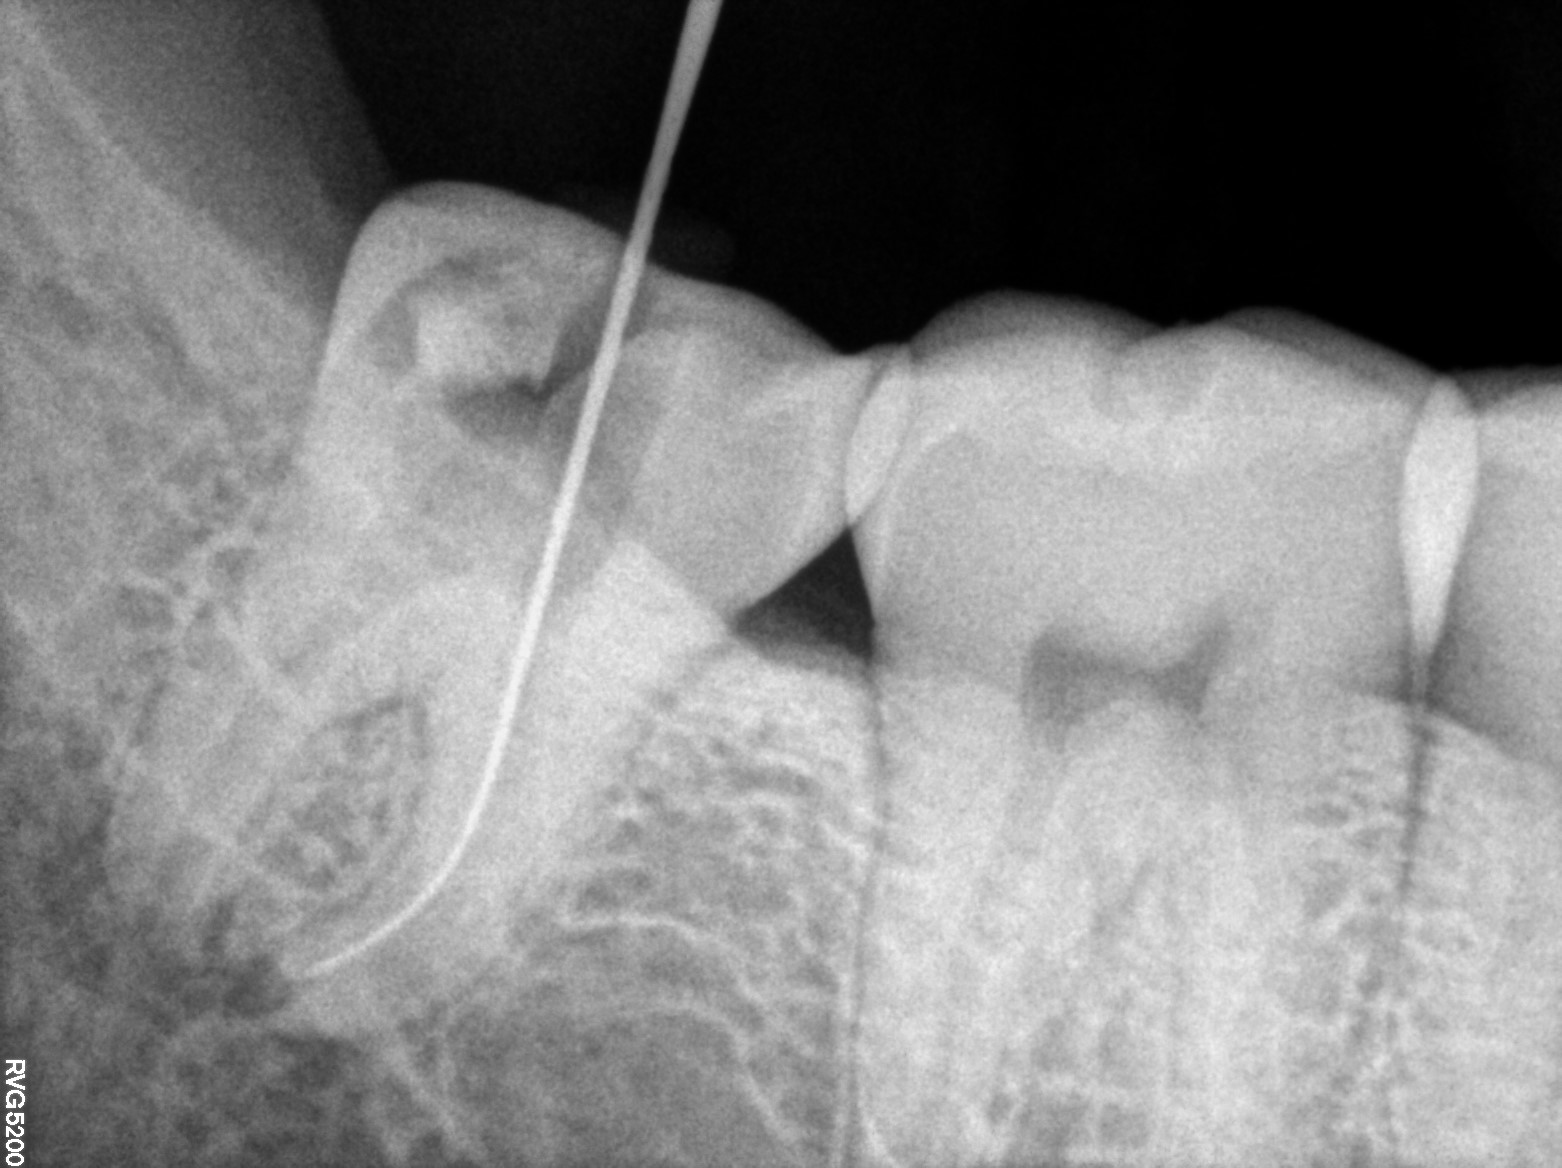

Dental Radiographs FHIR: DocumentReference · LOINC 24641-7

R55.jpg

24641-7